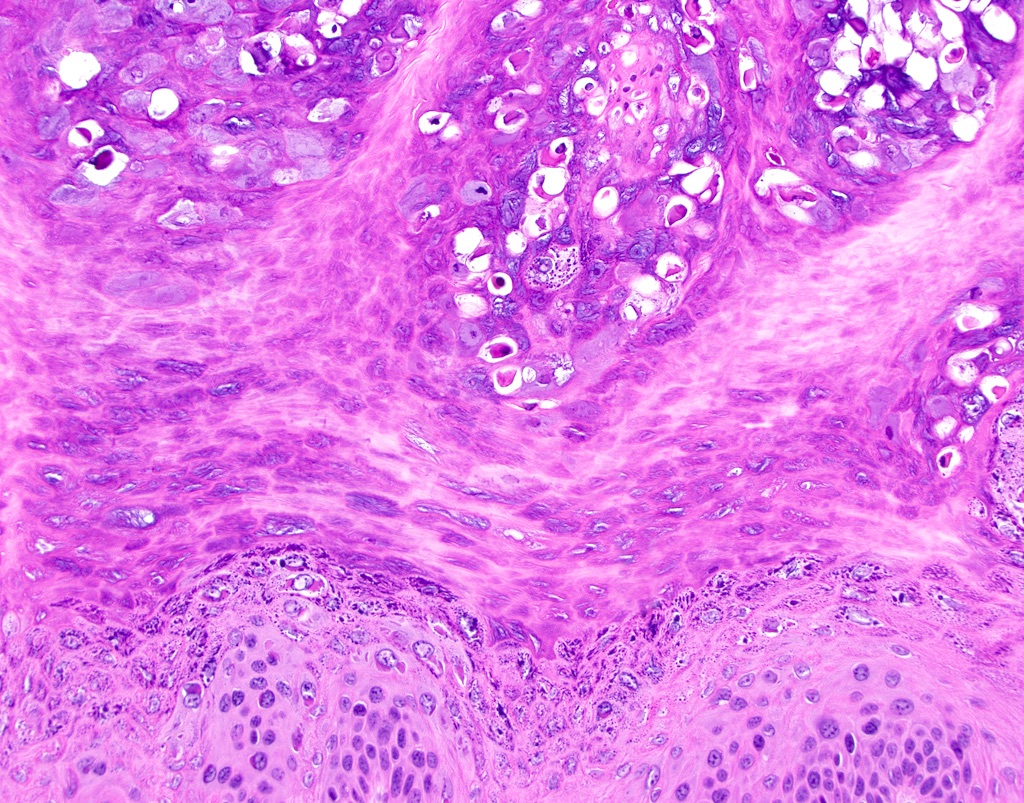

Microscopic (histologic) description

- Similar to cutaneous counterpart (Head Neck Pathol 2019;13:80)

- Prominent surface keratinization (often orthokeratin with superficial parakeratin tufts)

- Inward cupping of the rete pegs

- Exophytic / papillary fronds which form church spire-like peaks

- Hypergranulosis with coarse keratohyalin granules and potential eosinophilic intranuclear viral inclusions within the granular cell layer

- Koilocytosis within the superficial epithelial layers

Microscopic (histologic) images

C. Verruca vulgaris. The microscopic images show a well circumscribed, papillary epithelial proliferation with inward cupping of the rete ridges, prominent koilocytosis and prominent keratohyaline granules, which are all features of verruca vulgaris. Answers A and B are incorrect because condyloma acuminatum and squamous papilloma both lack prominent hypergranulosis while condyloma acuminatum exhibits broad, blunted papillary projections rather than the thin, hyperkeratotic projections seen above. Answer D is incorrect because verrucous carcinoma demonstrates broad, pushing rete ridges and lacks circumscription.

A patient presents with a white lesion on the hard palate. Microscopic examination shows a well defined proliferation of stratified squamous epithelium forming exophytic papillary fronds. The epithelium is covered by a thickened layer of dense orthokeratin, which forms church spires and hypergranulosis and koilocytosis are appreciated. The rete ridges demonstrate prominent inward cupping. What is the diagnosis?

C. Verruca vulgaris. Verruca vulgaris is characterized by a papillary epithelial proliferation with hypergranulosis, inward cupping of the rete ridges and koilocytosis, as described in the question. Answer A is incorrect because condyloma acuminata are not bright white clinically and lack prominent hypergranulosis. Answer B is incorrect because proliferative verrucous leukoplakia may look very similar to verruca vulgaris on small biopsies but proliferative verrucous leukoplakia is not well circumscribed clinically and not isolated. Additionally, proliferative verrucous leukoplakia does not show circumscription and inward cupping of the rete ridges histopathologically. Answer D is incorrect because verrucous carcinoma is traditionally larger clinically and demonstrates a pushing pattern of invasion without circumscription.